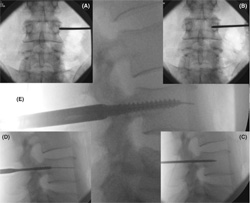

A brief description of this technique follows (Figures 1 , 2 ):

- The image intensifi er (II) is placed in the AP position. The

spinous process should be midline between the pedicles

to ensure a direct AP projection ( Figure 2 A).

- The position of the lateral aspect of the pedicle is marked on

the skin. Depending upon the depth of the tissue between

skin and pedicle, the skin incision should be made lateral

( Figure 1 A) so that appropriate angulation of the Jamshidi

needle can be made when inserting into the pedicle.

- The Jamshidi needle is placed through the skin incision

and “docked” onto the lateral aspect of the pedicle

(Figures 1 A, 2 ). This is called the “3 o-clock” position.

- The Jamshidi needle is advanced 20 to 25 mm into the

pedicle through the cortical bone, making sure the needle

remains lateral to the medial pedicle wall (Figures 1 A, 2 ).

A second Jamshidi needle can then be placed on the contralateral

side in a similar fashion.

- The II is then positioned in the lateral plane. The Jamshidi

needle should now be in the vertebral body, and therefore

“safe” with no risk of medial pedicle breach (Figures 1 A, 2 ).

- The stylet is then removed and a Kirschner (K)-wire is placed down the barrel of the Jamshidi needle. Once a

satisfactory penetration of the pedicle with the K-wire is

completed, the Jamshidi needle is removed, taking care

to maintain the position of the K-wire. A cannulated

scalpel is then passed over the K-wires to provide accurate

incisions that are long enough for the tissue guard.

- Tissue guards are then placed over the K-wires to perform

soft tissue dissection down to the level of the bone.

A pedicle screw tap is then placed down the trajectory

of the K-wire, through the pedicle into the trabecular

bone of the vertebral body, taking care the K-wire is not

moved during introduction ( Figure 2 ).

- The tap is then removed and the appropriate pedicle

screws (measurements based on preoperative CT scans)

are placed down the K-wire ( Figure 2 ), making sure not

to advance the K-wire beyond the anterior aspect of the

vertebral body. Confi rmation of pedicle screw placement

is achieved with II.

Figure 1. (A) Diagrams illustrating the

anatomical principles of percutaneous

pedicle screw insertion: views from top to

bottom: superior, posterior, lateral, superior.

First the initial skin incision is

made with the patients’ body habitus in

mind. Second, the Jamshidi needle is fi rst

‘‘docked’’ onto the lateral aspect of the

pedicle — ‘‘position 1’’ — on the anterior/

posterior image intensifi er (II) radiograph

projection. Third, the Jamshidi needle is

advanced 20 to 25 mm so that the needle

is beyond the medial border of the pedicle

and into the vertebral body – to ‘‘position

3.” Finally, the position is confi rmed by

lateral II radiograph projection before insertion

of the K-wire. (B) Grading system

for evaluation of screw position.

Figure 2. Percutaneous Technique (L4 Pedicle).

(A) Using AP x-ray, the Jamshidi needle

is ‘docked’ onto the facet/TP junction. (B)

The needle is advanced 20 to 25 mm making

sure that the tip of the Jamshidi is not beyond

the medial pedicle border. (C) Lateral

x-ray confi rms that the Jamshidi is within the

vertebral body. (D) Tapping the pedicle. (E)

Insertion of pedicle screw.